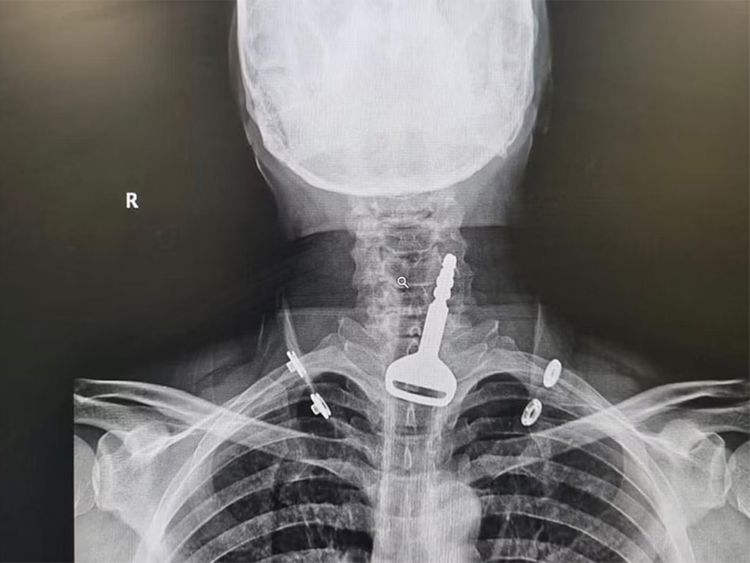

Σύμφωνα με το Gulf News, ο 49χρονος άνδρας εισήχθη στα επείγοντα του νοσοκομείου, όπου το προσωπικό παρατήρησε ότι είχε δυσκολία στην αναπνοή. Οι ακτινογραφικές εξετάσεις έδειξαν ένα κλειδί αυτοκινήτου μέσα στην αναπνευστική οδό και ο ασθενής είπε στους γιατρούς ότι το κατάπιε κατά λάθος ενώ έπαιζε με αυτό. Αποφασίστηκε ότι μια ενδοσκόπηση για την αφαίρεση του κλειδιού και την άρση της απόφραξης των αεραγωγών ήταν η καλύτερη λύση, αλλά το γεγονός ότι ο άνδρας ήταν καρδιοπαθής έκανε τη διαδικασία πολύ πιο περίπλοκη.

Ευτυχώς, η λαπαροσκοπική χειρουργική επέμβαση ήταν επιτυχής. Ο ασθενής νοσηλεύτηκε για λίγες ημέρες και έφυγε από το νοσοκομείο με το… αυτοκίνητο του.